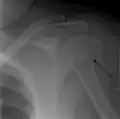

Fracture of the greater tuberosity of the humerus

Multi-fragmented, or comminuted fracture of the proximal humerus with involvement of the greater tuberosity